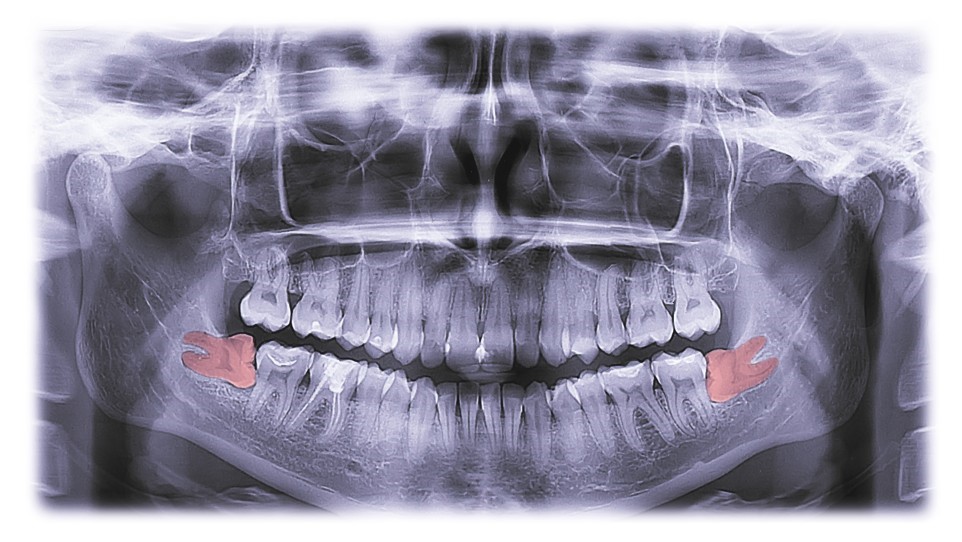

An OPG Showing Impacted lower Right And Left Wisdom Teeth

1. Impaction: Wisdom teeth often become impacted, meaning they don't have enough space to emerge or grow properly. This can lead to pain, infection, and damage to adjacent teeth.

2. Crowding: When there isn't enough room in the jaw for wisdom teeth to erupt correctly, they can push other teeth out of alignment, causing crowding and potentially undoing orthodontic work.